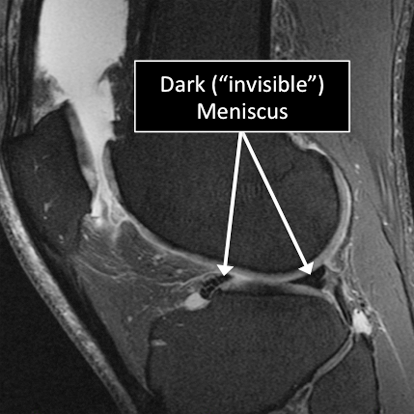

Why Translational MRI of the knee?

In the knee, as in many other parts of the body there are certain structures that can’t be seen (they look black or dark) with the standard MRI.

There are new “software” programs that allow us to see structures with different contrast (bright versus dark).

Some of these “invisible” or dark structures are unique to the knee (knee meniscus) and others are found in other parts of the body (e.g. cartilage, tendons, ligaments, cortical bone).

Knee MRI examinations using the standard MRI techniques (top) and translational MRI techniques (bottom).